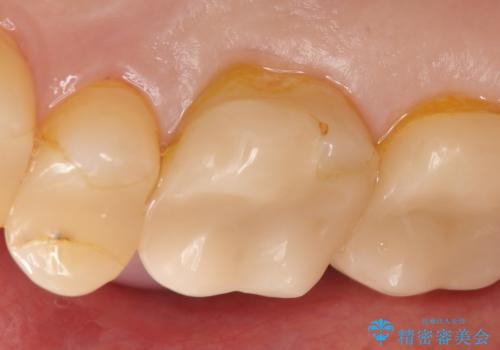

- 他院にて右上6の神経が死んでいるため根管治療が必要だと言われ当院にいらっしゃった方の症例です。

X線上で根尖病変を認めたため根管治療を行い、その後オールセラミッククラウンによる補綴を行いました